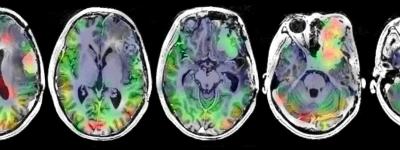

Panel showing 13C hyperpolarized imaging scans from a patient with a meningioma

HP-13C imaging of meningioma. Dynamically-acquired hyperpolarized carbon-13 (HP-13C) data obtained following [1-13C]pyruvate injection are shown for a patient with a hypermitotic meningioma, whose lesion is highlighted on the post-gadolinium T1-weighted imaging (top row). The temporally-summed signal from HP [1-13C]lactate demonstrates considerable lesion heterogeneity (second row). A modified lactate-to-pyruvate ratio thatpartially takes into account the non-metabolically-active vascular pool of [1-13C]pyruvate shows some of the relative glycolytic activity (third row). The conversion of pyruvate-to-lactate is also kinetically modeled as a rate constant (kPL) to similarly highlight glycolytic activity over the lesion (fourth row). Image courtesy of Yan Li, PhD.